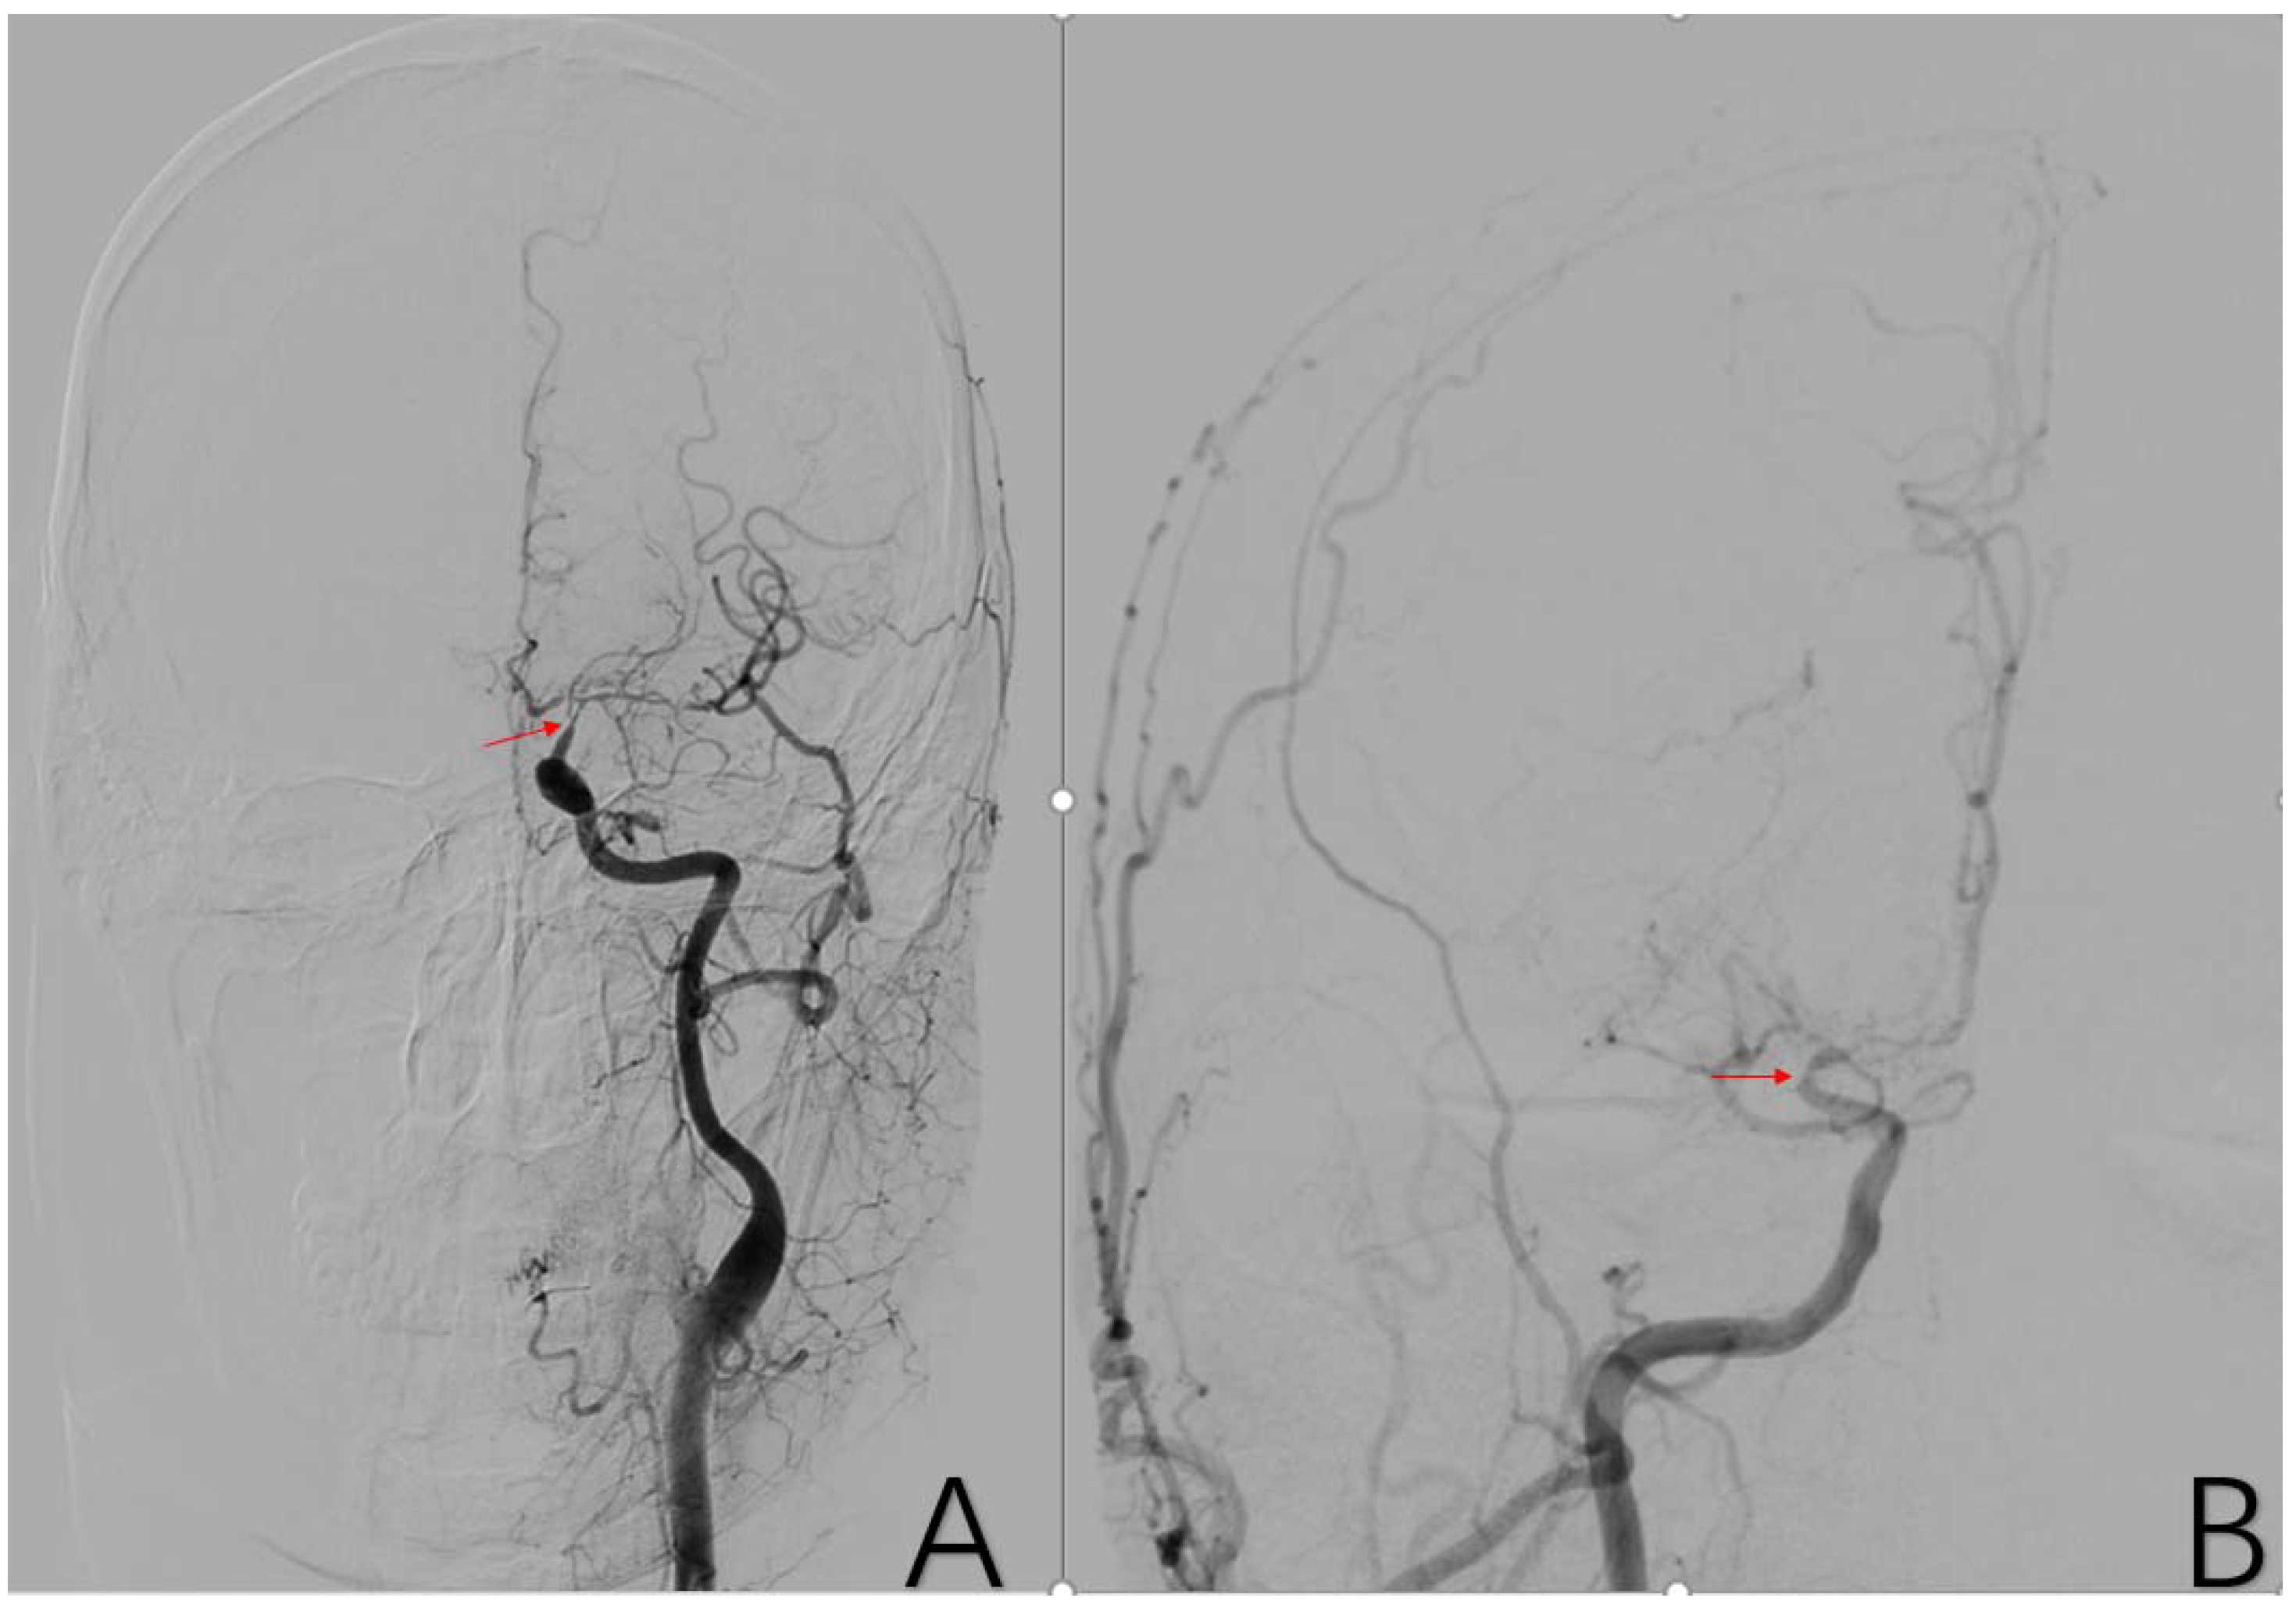

2.3.7. Factor 2 A1 Stenosis

2.3.8. Factor 3 M1 Stenosis

2.3.9. Factor 4 PCA Anomaly

2.3.10. Factor 5 Posterior Circulation Compensation

2.3.11. Factor 6 Unstable Compensation

2.3.12. Factor 7 Extracranial Arterial Compensation